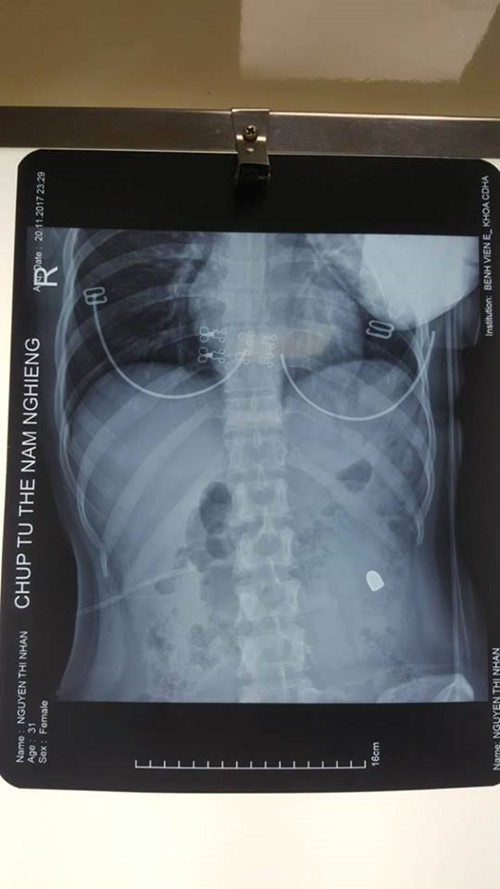

| Kết quả chụp X-Quang thấy đầu đạn nằm trong bụng cô gái. |

| Các bác sĩ Bệnh viện E mổ lấy đầu đạn trong bụng, cứu sống cô gái. |